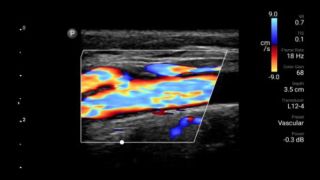

Disminuya las complicaciones de las inserciones de CVC

La guía por ultrasonido en tiempo real puede mejorar la precisión y la seguridad de las inserciones de CVC.

Transductor de matriz lineal de banda ancha Lumify L12-4

• Rango extendido de frecuencias de operación entre 12 y 4 MHz • Tamaño de apertura: 34 mm • 2D, Doppler orientable a color, Modalidad M, XRES avanzado e imágenes armónicas multivariables, SonoCT • Imágenes de alta resolución para aplicaciones superficiales: tejidos blandos, vasculares, superficiales, musculoesqueléticos y pulmonares • Marcador de línea central • Transductor USB-C con cable reemplazable